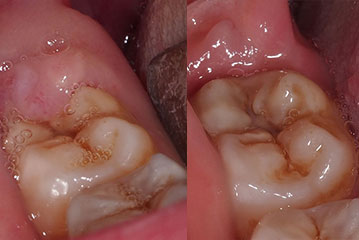

Treating Large Lumps in the Gums

Gum disease when left untreated can eventually result in the jaw bone dissolving away to make teeth become loose and potentially fall out; but it can also cause very severe swellings and lumps as well.